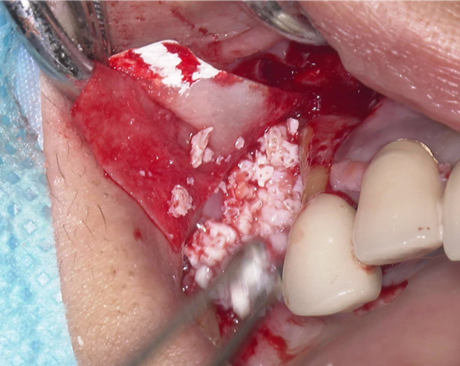

②血液成分とカルシウム材料により骨造成をしました。

術前ではインプラントを埋入する骨組織はほとんど有りませんが、

術後完全に骨内に埋入出来ました。